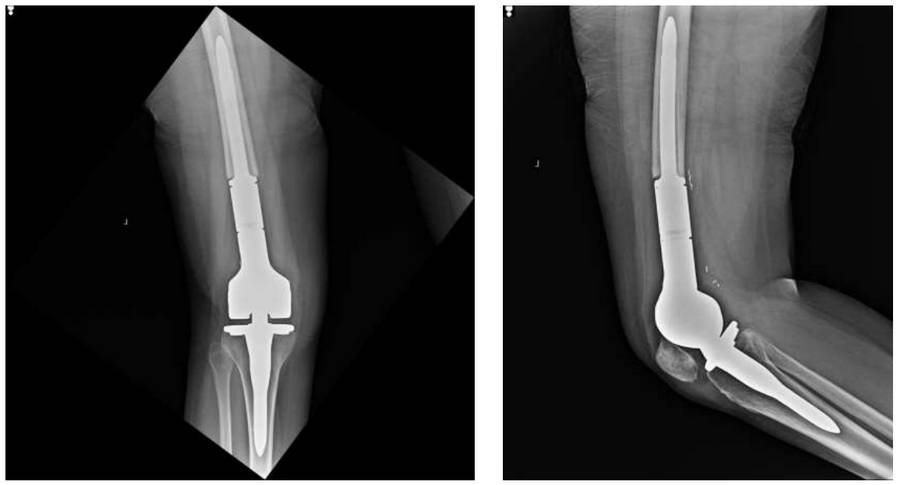

Post-Surgery: The X-ray shows the placement of a distal femur tumor prosthesis after resection.